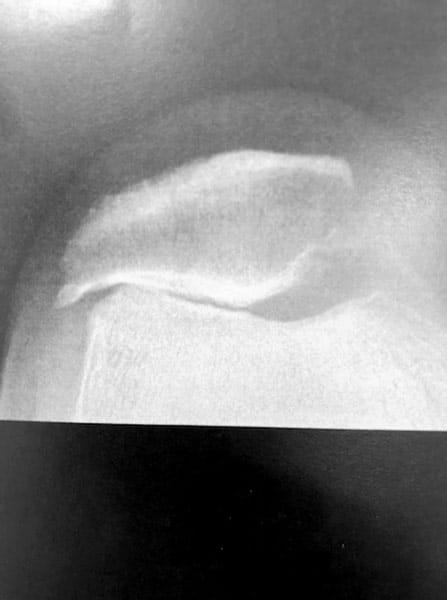

Arthrose externe de rotule isolée chez une patiente jeune, âgée de 45 ans.